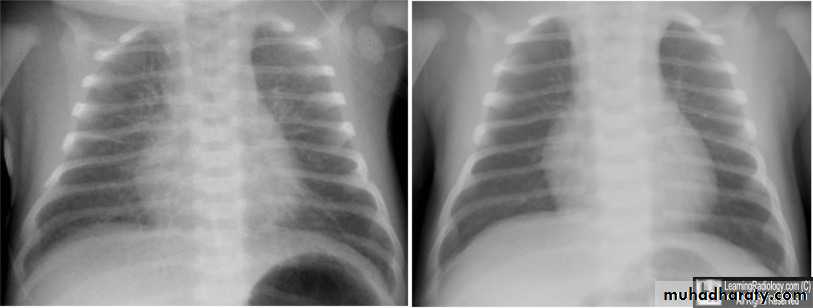

TTN CXR

History of full term delivered by C-section, or low birth WT baby born by rapid precipitous labor or IDM baby develops tachypnea within first 3 hours of birth,CXR showing; hyperinflation, more aerations , perihilar prominent vascular lung marking, interstitial streaks of fluid and fissures shows fluid lines, in addition to mild cardiomegaly, should suggest TTN. Low Spo2<90%. -------------------------------------

To differentiate it from other causes like RDS is mainly by the exclusions; by nature of delivery, the maturity of baby <32wks in RDS , and the course of the tachypnea(severity and the duration in RDS more severe and takes longer course up to 1 wk) x-ray in RDS; shows less aerations, whitening of lung ,and presence of bronchogram .